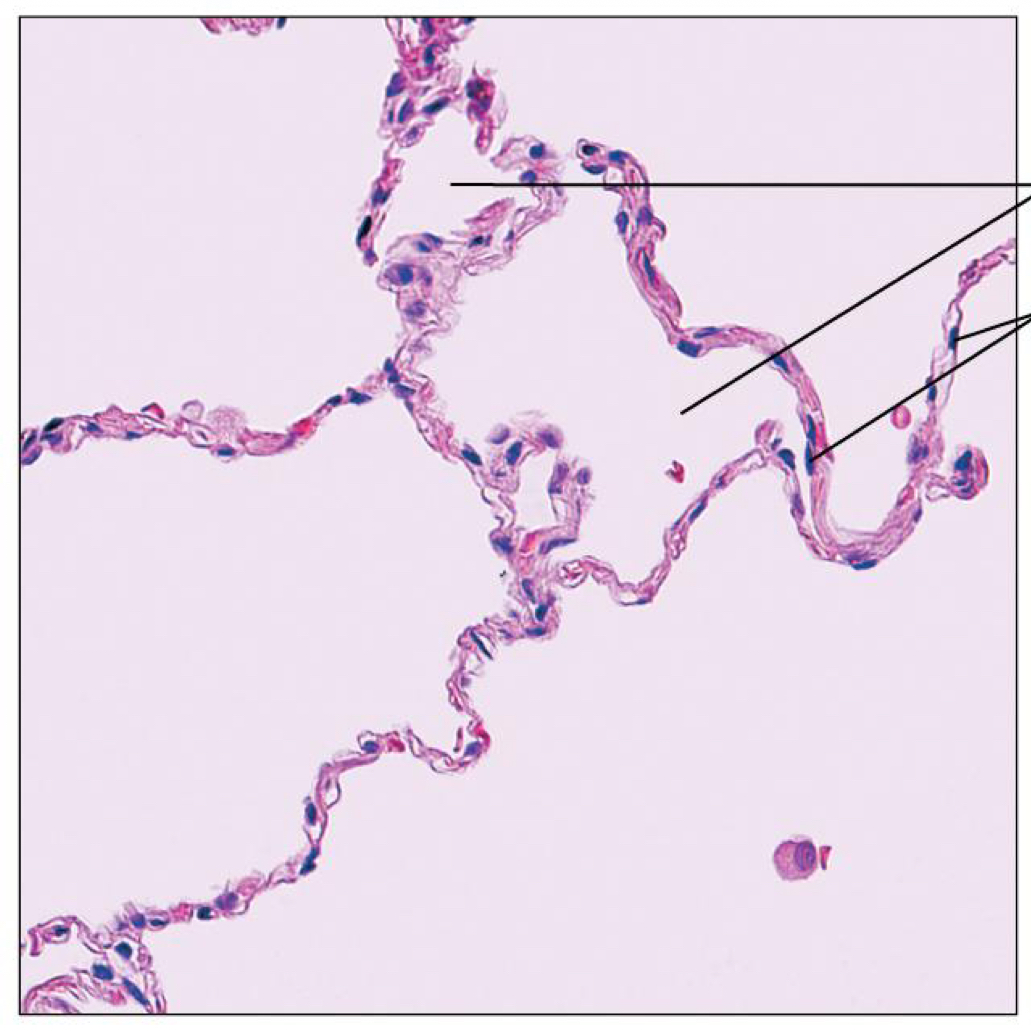

What are thIs tissue

Simple squamous epithelium

Simple squamous epithelium Function

Allows. Materials to pass (diffusion), filtration, secretes lubricating substances

Simple squamous epithelium Location

Kidney, air sacks of lungs, heart lining, lymphatic vessels